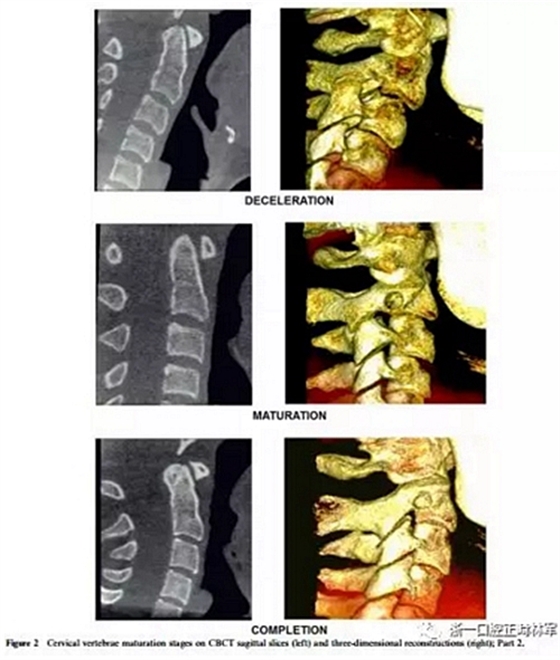

將CBCT三維重建和矢狀切片隨機(jī)分組,并使用軟件OsiriX®(The Osirix Foundation,Geneva,Switzerland)評(píng)估兩次。這些圖像在MacBook Pro(Apple Computer Inc.,Cupertino, CA)。使用OsiriX軟件,通過使用三維成像技術(shù),從醫(yī)學(xué)文件中的數(shù)字成像和通信獲得三維圖像重建。通過多平面重組獲得的矢狀切面是通過將光標(biāo)定位在沿中腭縫線和前鼻棘中心的線上來選擇的。為了避免視疲勞,每天只評(píng)估20幅圖像。評(píng)估分階段進(jìn)行,每次選擇一種展覽模式,第一次和第二次。CBCT圖像在昏暗的房間里,在具有亮度和對(duì)比度恒定特征的屏幕上進(jìn)行解讀,允許利用軟件的縮放,亮度和對(duì)比度工具來增強(qiáng)診斷。每個(gè)展覽模式的圖像解讀最短時(shí)間為15天。在第一次評(píng)估后1個(gè)月,考慮到3D重建和矢狀切片(圖1和圖2),讀片員再次讀片,獲取72條記錄。

4、減速期(頸椎成熟指數(shù)-4)

預(yù)計(jì)增長(zhǎng)10-25%。椎骨C2,C3和C4的下部邊界呈現(xiàn)明顯的凹陷,并且椎骨C3和C4的體部呈現(xiàn)近似正方形的形狀。

5、成熟期(頸椎成熟指數(shù)-5)

這對(duì)應(yīng)于椎骨成熟的最后階段,預(yù)計(jì)5-10%的增長(zhǎng)。在椎骨C2,C3和C4上觀察到更明顯的凹陷。后者有方形的體部。

6、定型(頸椎成熟指數(shù)-6)

現(xiàn)階段增長(zhǎng)已經(jīng)完成。椎骨C3和C4的體部具有比水平尺寸和下邊界更大的垂直,下邊界保持明確的凹陷。